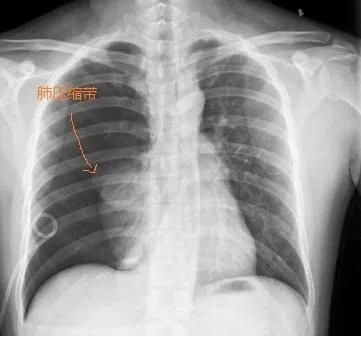

临床症状除了胸痛,还可以伴随有呼吸困难、刺激性咳嗽等,若出现上述症状,记得要马上就诊,门诊行直立位胸部正侧位片便可诊断,此外CT常常可以准确地显示小肺大泡的数目、大小和位置,有利于决定治疗方案。

这是胸片上看到的肺,被漏出来的气体给压瘪了,留下了一条清晰的肺压缩带……

对于平素健康无症状的患者,胸片提示肺萎陷小于30%,可以观察等待气胸自愈吸收,对于大于30%气胸的患者,一般会先穿刺抽气或胸腔闭式引流处理,临床上大多采取胸腔闭式引流为主,可以避免反复穿刺抽气造成的痛苦。如采用胸腔闭式引流术后仍有大量漏气,肺仍不能完全膨胀复张者或中等量或大量气胸需外科手术治疗,就好比车轮胎爆胎就要补胎一样。